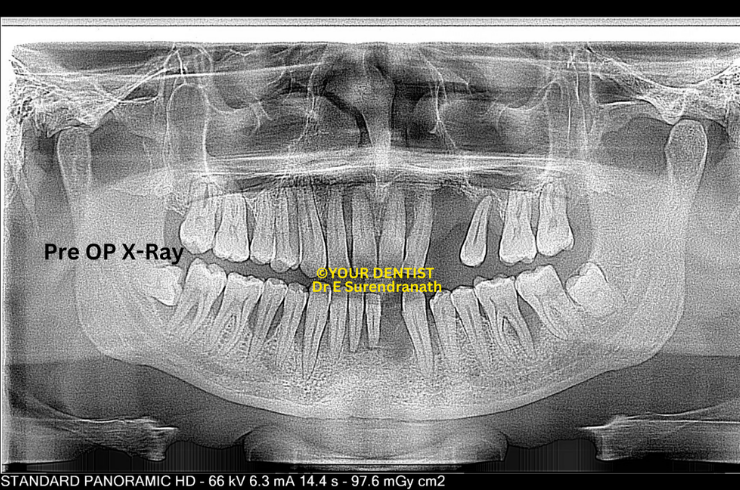

Patzi implant protocl - Pre OP Xray